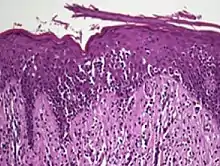

Histology

Histopathology of Pautrier microabscesses in cutaneous T cell lymphoma.

The criteria for the disease are established on the skin biopsy by the presence of the following:[18]

• Presence of cancer cells with twisted contours (cerebriform nuclei)

• In the patch and plaque stages, the cancer cells are seen in the epidermis (the most superficial layer of skin).[19] This is referred to as epidermotropism.

• Pautrier's microabcesses, aggregates of four or more atypical lymphocytes arranged in the epidermis. Pautrier microabcesses are characteristic of mycosis fungoides but are generally absent.

• In the tumour stage, the cancer cells move into the dermis (the deeper layer of skin)[19]

• Large cell transformation, where clonally identical lymphocytes in the lesion exhibit hypertrophy. In transformed cells, presence of the CD30 receptor is associated with improved survival[20]